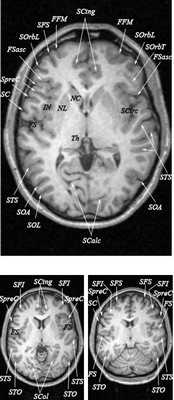

Анатомия головного мозга в МРТ изображении

МРТ головного мозга. Т2-взвешенная аксиальная МРТ. Цветовая обработка изображения.

Знание анатомии мозга очень важно для правильной локализации патологических процессов. Ещё более важно оно для изучения самого мозга с помощью современных «функциональных» методов, таких как функциональная магнитно-резонансная томография (fMRI), и позитронно-эмиссионная томография. С анатомией мозга мы знакомимся ещё со студенческой скамьи и существует множество анатомических атласов, в том числе и поперечных сечений. Казалось бы, зачем ещё один? На самом деле, сравнение МРТ срезов с анатомическими приводит к множеству ошибок. Это связано как со специфическими особенностями получения МРТ изображений, так и с тем, что строение мозга очень индивидуально.

Представленная страница сайта основана на специальном изучении МРТ головного мозга здоровых лиц. Для этого изображения получали с минимальной величиной воксела (1 мм в каждом измерении), что исключало наслоения борозд. Каждая из структур прослеживалась в трёх реконструированных плоскостях путём её выделения с помощью компьютерной программы. Мы рассматривали различные анатомические варианты, что обсуждается в работе. В результате, учитывая вариабельность строения мозга, подобран условно «стандартный» мозг. Поскольку на сайте нереально представить 128 срезов в каждой из основных плоскостей, мы ограничились только каждым пятым срезом. Основные срезы в поперечной плоскости даны без наклона назад (угол 0º). Под ними для представления о изменении соотношения анатомических структур демонстрируются срезы, выполненные на тех же уровнях, но с наклонами назад -15º и -30º.

Список сокращений

Борозды

Междолевые и срединные

SC - центральная борозда

FS - Сильвиева щель (латеральная борозда)

FSasc - восходящая ветвь Сильвиевой щели

FShor - поперечная борозда Сильвиевой щели

SPO - теменно-затылочная борозда

STO - височно-затылочная борозда

SCasc - восходящая ветвь поясной борозды

SsubP - подтеменная борозда

SCing - поясная борозда

SCirc - круговая борозда (островка)

SpreC - предцентральная борозда

SparaC - околоцентральная борозда

SFS - верхняя лобная борозда

FFM - лобно-краевая щель

SOrbL - латеральная глазничная борозда

SOrbT - поперечная глазничная борозда

SOrbM - медиальная глазничная борозда

SsOrb - подглазничная борозда

SCM - мозолисто-краевая борозда

SpostC - постцентральная борозда

SIP - внутритеменная борозда

STS - верхняя височная борозда

STT - поперечная височная борозда

SCirc - круговая борозда

SCalc - шпорная борозда

SOL - латеральная затылочная борозда

SOT - поперечная затылочная борозда

SOA - передняя затылочная борозда

Поперечные (аксиальные) МРТ срезы головного мозга